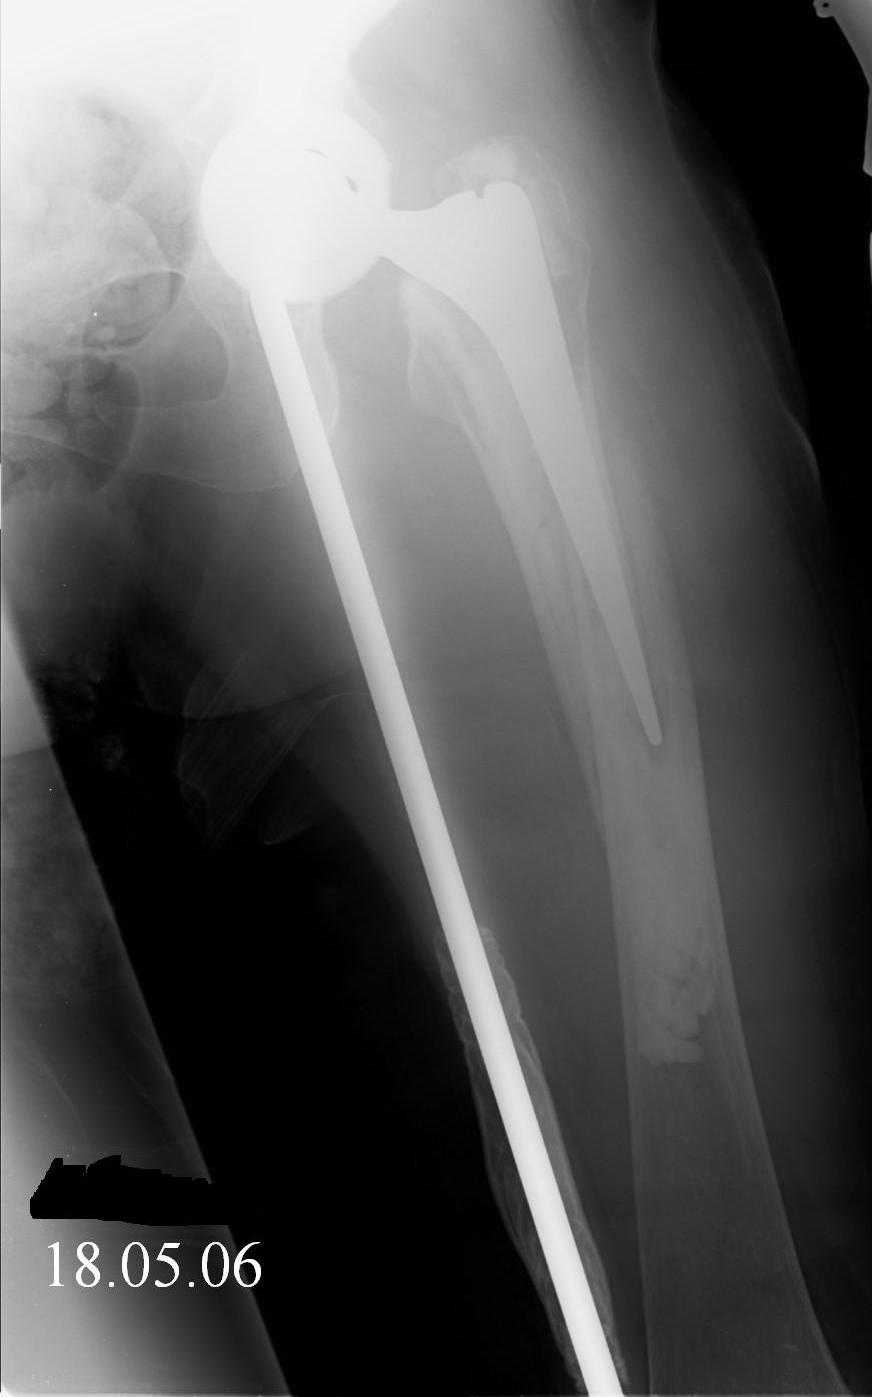

Re: Перипротезный перелом

Hello! This is just illustration in one of the choice of treatment